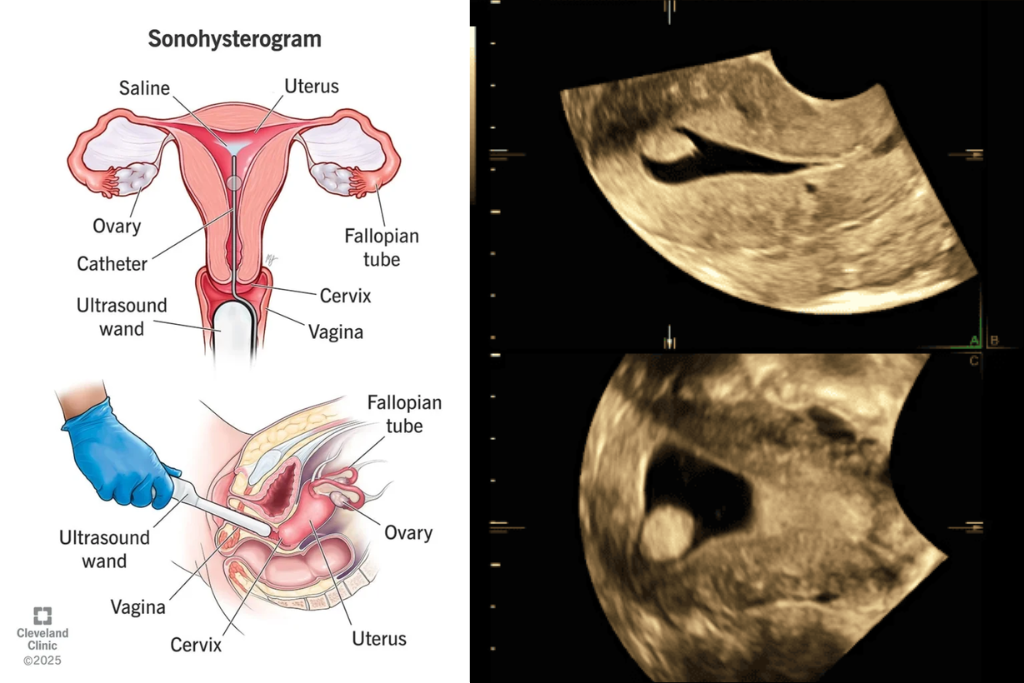

- Saline Infusion Sonography (SIS): A special procedure using saline to assess the uterine cavity for polyps or scars.

SIS (Saline Infusion Sonography)

An ultrasound in which saline is injected into the uterus to examine its inner lining clearly.

Why are HyCoSy and SIS tests recommended?

These tests help in identifying fallopian tube blockages and uterine abnormalities, which are common causes of infertility, allowing better treatment planning.